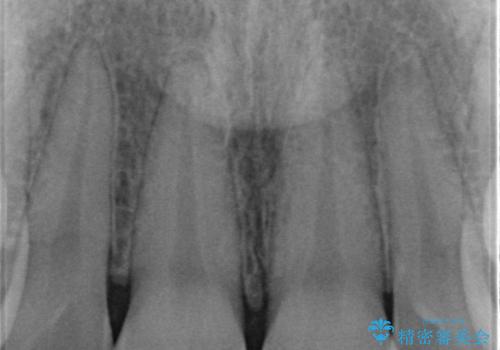

すり減った前歯の形態回復

- すり減ってしまった前歯の審美性の回復を希望され来院されました。

何度かレジン修復を試みたものの、脱離しやすく変色も気になる、とのことでセラミッククラウンによる審美性の回復を計画します。

右側は、クラウンにせず可及的に形態を整えることのみでの対応としました。